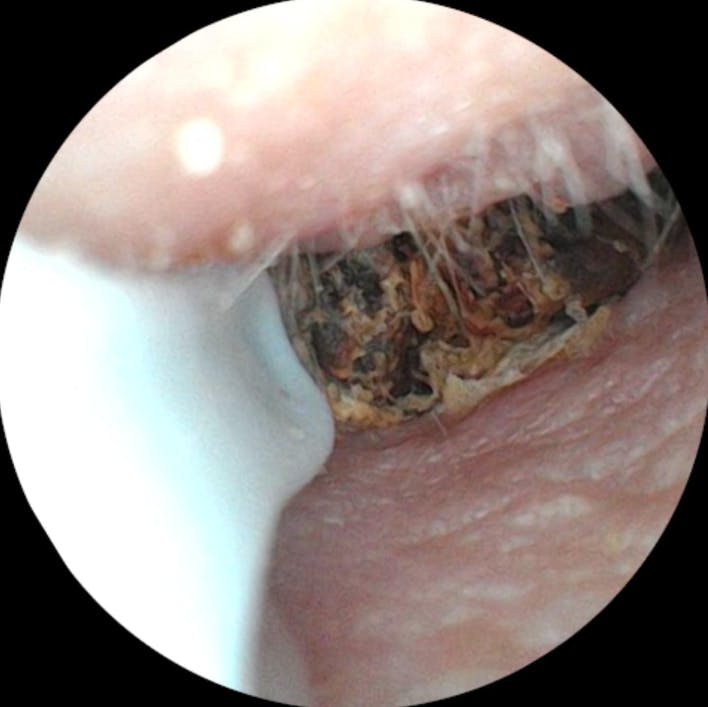

Ich bin wirklich überraschend begeistert von diesem Ohrenendoskop. Die Handhabung ist kinderleicht, die Verbindung zum Smartphone hat auf Anhieb funktioniert und die Bildqualität ist überraschend gut – gestochen scharf und detailreich. So konnte ich mir das Ohrinneres problemlos anschauen und erkennen, was los ist.

Besonders praktisch finde ich das schlanke Design und die integrierte Beleuchtung – dadurch sieht man selbst kleine Details sehr klar. Auch die mitgelieferten Aufsätze und Werkzeuge sind gut verarbeitet und machen die Anwendung noch einfacher und hygienischer.

Ich habe eine starke Ohrenschmalzproduktion und es entstehen regelmäßig Propfen, die in der Vergangenheit regelmäßig vom Ohrenarzt entfernt werden mussten.

Mit diesel Gerät kann ich selbst in regelmäßigen Abständen das Ohr vom gröbsten Ohrenschmalz befreien. Mit diesem Gerät tut es überhaupt nicht weh, die Aufnahmen der Kamera sind sehr gut. Mit etwas Geduld, Übung und Vorsicht kann man das Ohr wirklich sehr gut reinigen, ohne es zu verletzen. Ich kann das Produkt ohne Vorbehalte weiterempfehlen und würde es wieder kaufen.